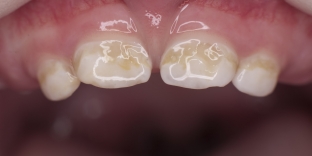

- The initial stage develops at 10-20 months of age. It is characterized by the appearance of white spots on the vestibular surface of the upper incisors. These are the centers of enamel demineralization. A white line is visualized in the region of the neck of the tooth. There are no subjective sensations. Carrying out treatment – preventive measures at this stage can prevent the further development of bottle caries.

Bottle caries develops with circular spread – around the crown of the tooth. Yellow – brown or black spots indicate the progression of bottle caries. There is also an increased sensitivity to hot or cold food.